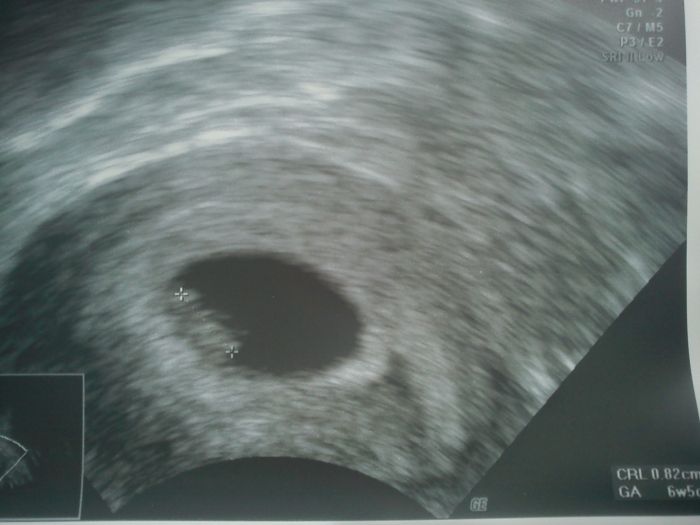

Ahoj holky, tak se hlásíme - jsme 82mm velcí, srdíčko krásně tluče, vše se zdá být tak jak má - podle utz 6plus5/podle ms 7plus3 - obrázek přikládám!! Je tam zdá se jedno a já sem celá z toho roztřepaná...no prostě krásný gumídeček náš další